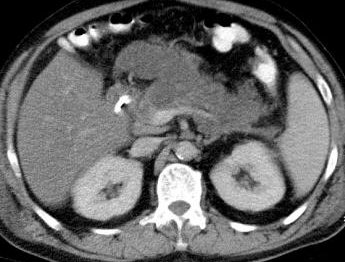

Abdominal CT scan. Hemorrhagic rupture of a simple hepatic cyst without active hemorrhage. The presence of free intraperitoneal fluid is noted (Courtesy Dr. V. Penopoulos)